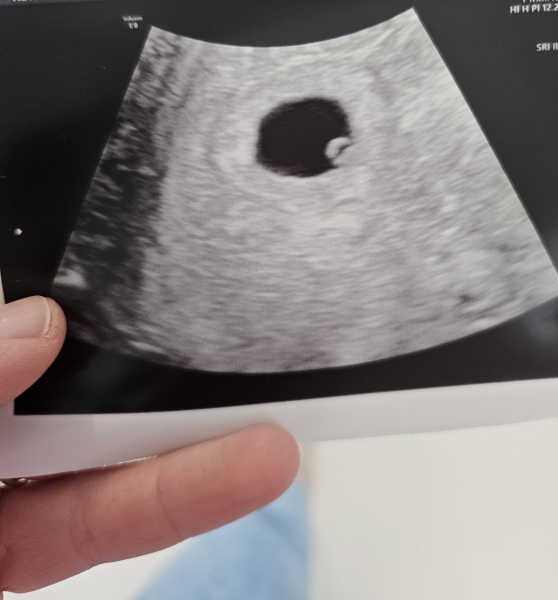

Just a little update been for my other scan today was shocked with the change. Yoke seen so they have discharged me from them now feel relieved xx